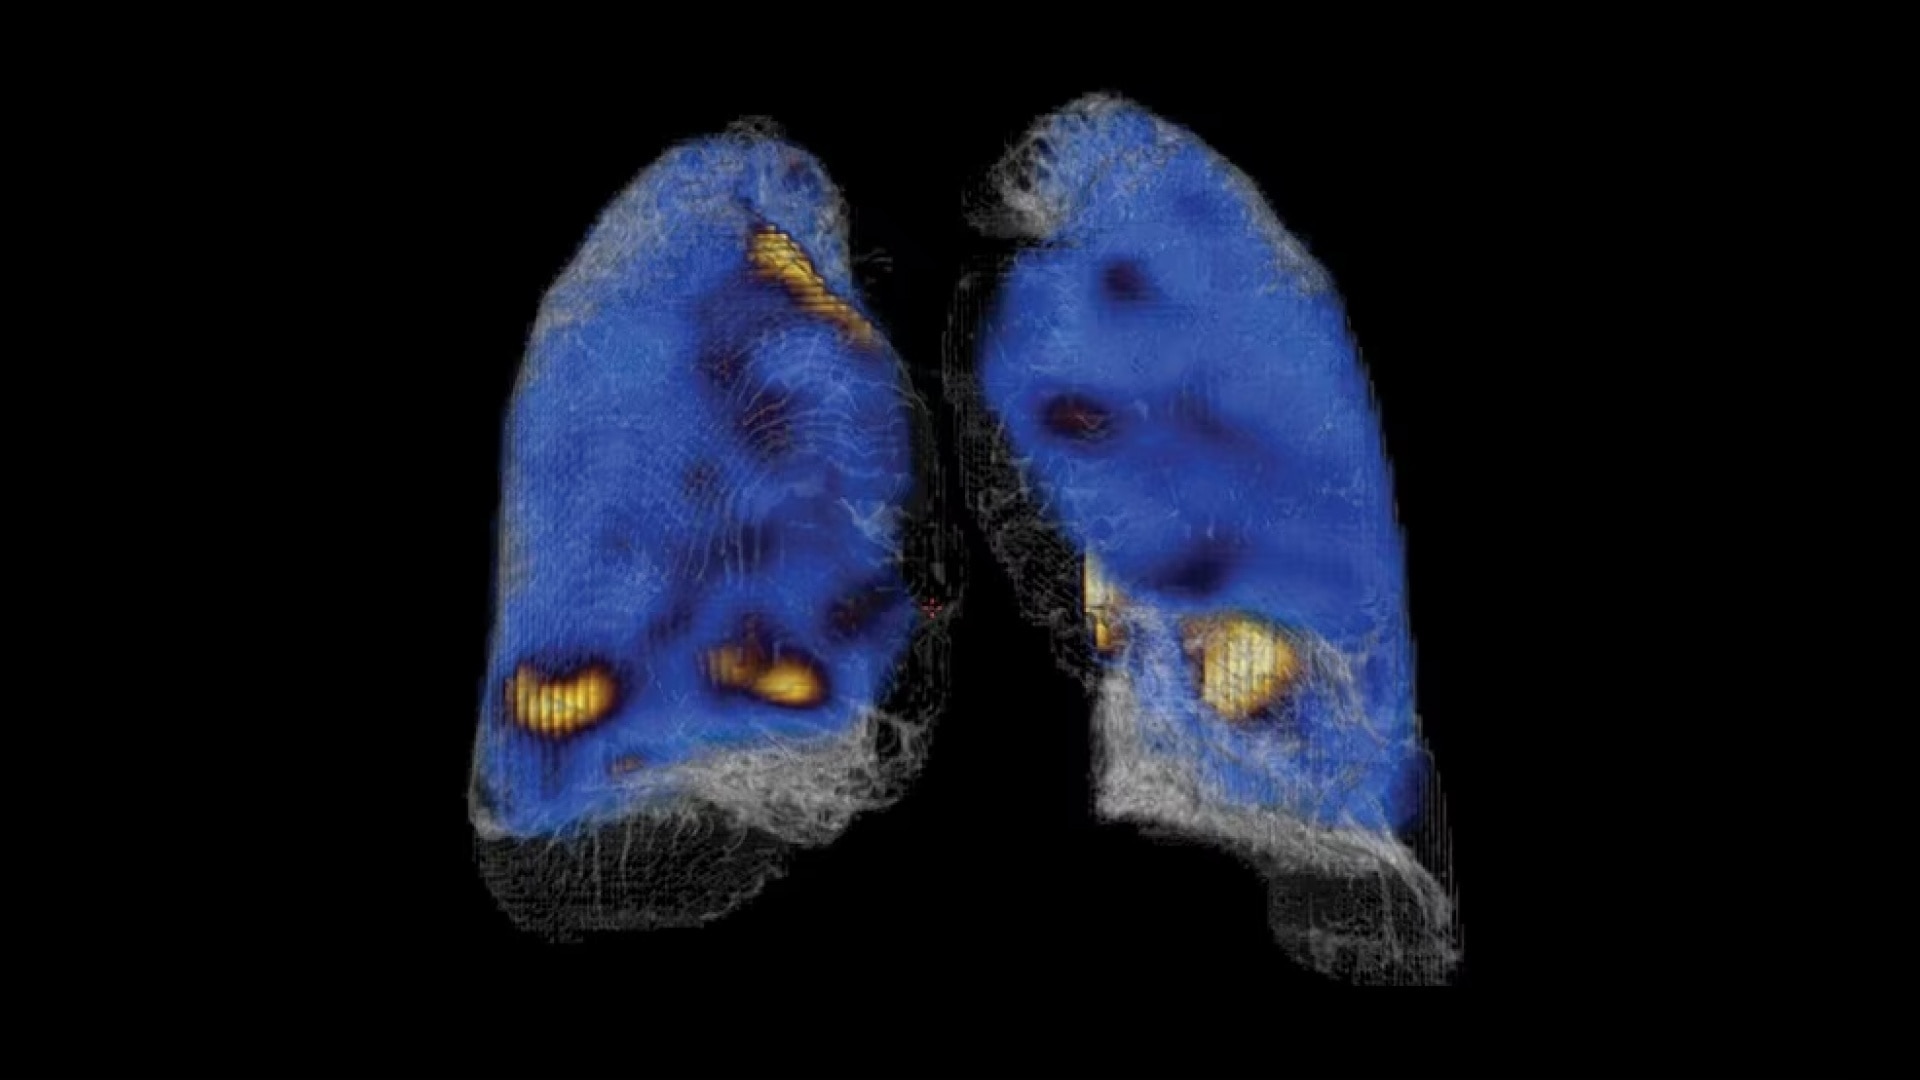

A fully digital vision for nuclear medicine

A fully digital vision for nuclear medicine

Additionally, this is a premium SPECT/CT system that delivers the added flexibility of a standalone CT that includes advancements in dose and metal artifact reduction. And it delivers the accurate, reproducible results referring physicians require in a comfortable and streamlined exam experience.